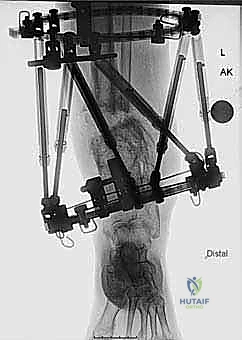

المرحلة الثانية: تركيب المثبت الخارجي (Frame Application)

قبل قطع العظم، يقوم الدكتور هطيف بتركيب الهيكل الخارجي (الإليزاروف أو الفريم الدائري).

1. يتم إدخال أسلاك دقيقة جداً (K-wires) ومسامير نصفية (Half-pins) عبر الجلد إلى العظم بدقة متناهية لتجنب الأعصاب والأوعية الدموية.

2. يتم تثبيت هذه الأسلاك في الحلقات المعدنية الخارجية. حلقة أو حلقتين فوق مكان القطع المخطط له، وحلقة تحته (في الجزء السفلي من الساق والقدم إذا لزم الأمر).

3. يتم التأكد من استقرار الهيكل الخارجي بالكامل.

المرحلة الثالثة: قطع عظمة الشظية (Fibular Osteotomy)

للسماح للظنبوب (العظمة الرئيسية) بالتحرك والتصحيح، يجب أولاً قطع عظمة الشظية. يتم ذلك عبر شق جراحي صغير جداً (حوالي 1-2 سم) في الثلث السفلي أو الأوسط من الساق.

المرحلة الرابعة: قطع العظم عبر الجلد (Percutaneous Tibial Osteotomy)

هنا تتجلى مهارة الجراحة بأقل تدخل:

1. يُجري الدكتور هطيف